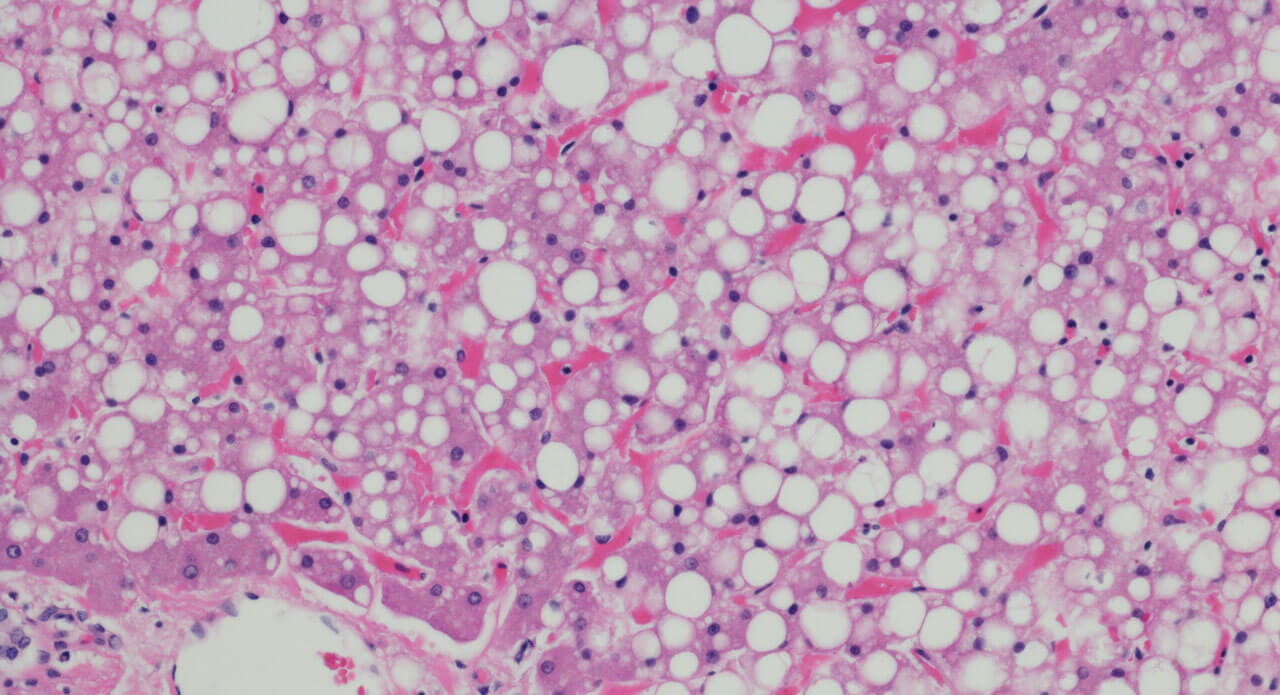

That is the current state of affairs for a disease known as NASH (non-alcoholic steatohepatitis) in which the liver is damaged by inflammation due to a buildup of fats. NASH is a progressive subtype of non-alcoholic fatty liver disease (NAFLD). Associated risk factors for NAFLD, NASH and the later stages of NASH (liver fibrosis and cirrhosis) are obesity, Type 2 diabetes, and the collection of symptoms known as metabolic syndrome.

The main way that damage manifests itself in the liver is something called fibrosis— a thickening and scarring of the tissue that can ultimately lead to cirrhosis and liver failure.